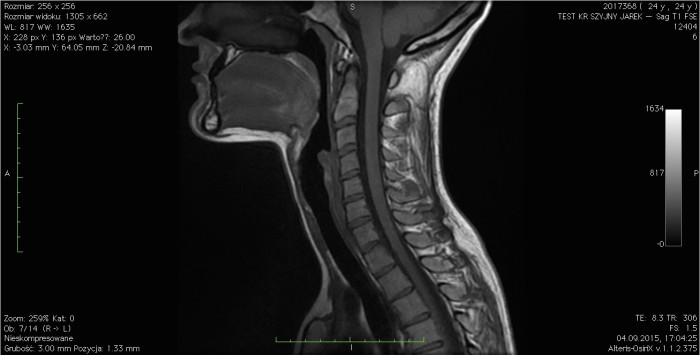

MRI.

Rezonans magnetyczny jest zdecydowanie najbardziej uniwersalnym badaniem dodatkowym używanym w diagnostyce ortopedycznej. Pozwala on na ocenę zarówno wszystkich tkanek miękkich, jak i elementów kostnych danej okolicy i zazwyczaj jest w stanie zastąpić RTG oraz USG. Do jego wykonania, w przeciwieństwie do tomografu komputerowego, nie używa się promieni rentgenowskich, dzięki czemu można je powtarzać wielokrotnie w krótkich odstępach czasu.

Najczęstszymi przypadkami, w których wykonuje się badanie MRI są urazy skrętne, naderwania, zerwania więzadeł (np. więzadła krzyżowe kolana), urazy kręgosłupa, diagnostyka tkanek położonych głęboko poza zasięgiem ultrasonografu. Nie jest to jednak badanie idealne. Nie pozwala ono na dynamiczną ocenę tkanek, a koszt jego wykonania przewyższa kilkukrotnie cenę wcześniej wymienionego rentgena i USG. Również jego wykonanie nie jest dla pacjenta komfortowe, ponieważ wymaga utrzymania nieruchomej pozycji przez około 20 – 45 minut. Niemniej jednak diagnostyka za pomocą MRI jest bardzo dokładna i zdecydowanie ułatwia pracę lekarzom i fizjoterapeutom.

Badanie rezonansem magnetycznym bardzo szczegółowo obrazuje wszystkie rodzaje tkanek.